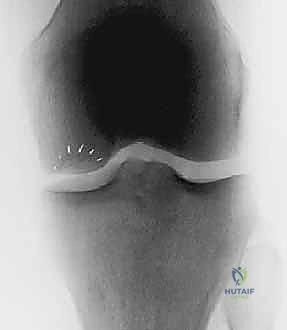

- Plain Radiographs: Weight-bearing anteroposterior (AP), notch, sunrise, and lateral views. While cartilage itself isn't visible, we assess joint space narrowing, bony defects, and overall limb alignment. Full-length lower extremity radiographs are crucial for assessing mechanical axis and planning potential osteotomies.

FIG 3 • and AP ( B ) radiographs of osteochondritis dissecans.